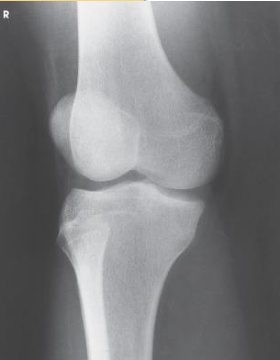

Which knee projection is this

Lateral knee

Patient position for lateral knee is

turned toward affected side, flexed, brought forward

Femoral epicondyles and patella are what to the IR during lateral knee

perpendicular

CR angle in lateral knee is

5 to 7 degrees cephalic

CR enters where for a lateral knee

knee joint 1 inch distal to medial femoral epicondyle

Open patellofemoral joint space seen in

For lateral knee, over rotation results in

less superimposition

For lateral knee, under rotation results in

more superimposition